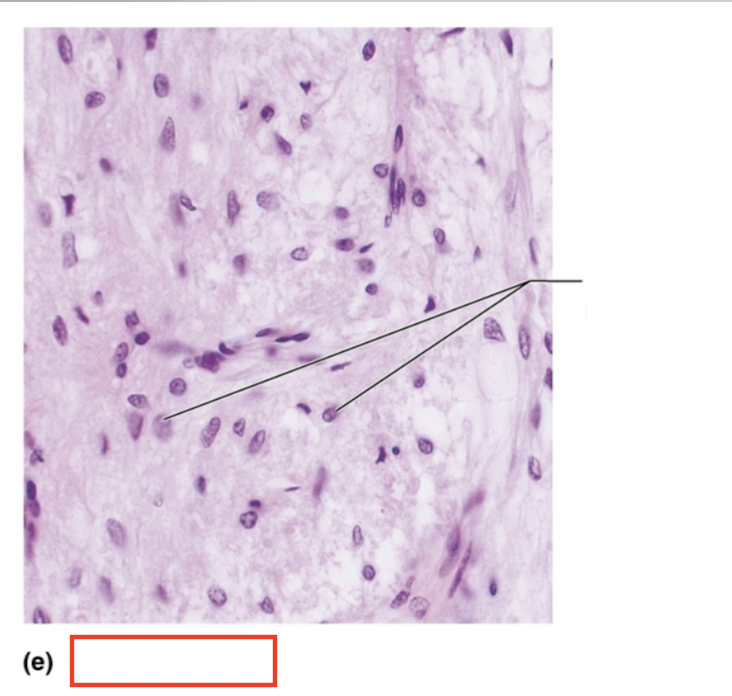

What structure is highlighted?

pituicyte nuclei

What tissue is shown?

posterior pituitary

What hormones are synthesized by the hypothalamus and stored in the posterior pituitary?

oxytocin and ADH

What is the target organ and effects of oxytocin?

uterus and mammary glands; stimulates powerful uterine contractions during birth and stimulates milk ejection (let down) in lactating mothers

What is the target organ and effects of ADH?

kidneys; stimulates the kidneys to reabsorb more water, reducing urine output and conserving body water